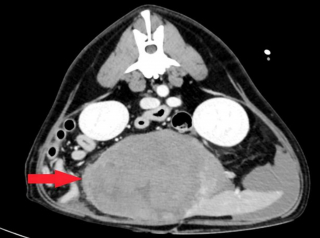

Chez le vétérinaire, toutefois, le diagnostic était tout autre ; le Golden Retriever avait une grosse tumeur à la rate. Le praticien a orienté Jane Gallacher vers l’équipe de la clinique vétérinaire VSS (Veterinary Specialists Scotland) à West Lothian.

La spécialiste Joanna McCagherty a donc pris le relais. Elle a expliqué à Jane Gallacher que Marty devait être opéré et que l’intervention serait particulièrement complexe et risquée. Le quadrupède pouvait y laisser la vie.

Pendant l’opération, la rate s’est rompue à cause de la taille de la tumeur, mais le saignement n’était pas important et le chien y a survécu.